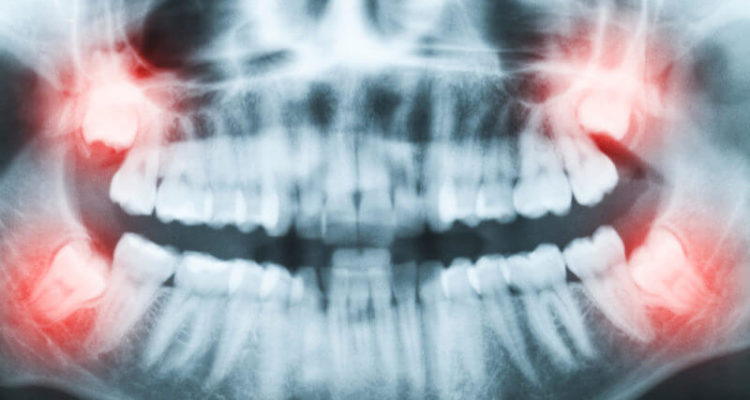

Стоматологи розповіли всю правду про зуби мудрості або «вісімки». Виявилося, людині не обов’язково йти на видалення.

Люди можуть чудово себе почувати з зубами мудрості, якщо вони здорові, не доставляють занепокоєння, повністю і правильно прорізалися, доступні для чищення.

У деяких випадках лікарі рекомендують відразу позбутися від “вісімок”. По-перше, до стоматолога потрібно звернутися при недостатньому прорізуванні, болі і набряку щелепної кістки або ясен, ризик розвитку карієсу.

По-друге, видалення рекомендується при неправильному розташуванні зубів, наприклад, коренем в бік. Через тиск на сусідні зуби відбудеться зміщення всього ряду. У серйозних випадках може знадобитися операція. На відновлення після видалення зазвичай йде близько двох тижнів. На цей період медик може призначити болезаспокійливі і протизапальні препарати.